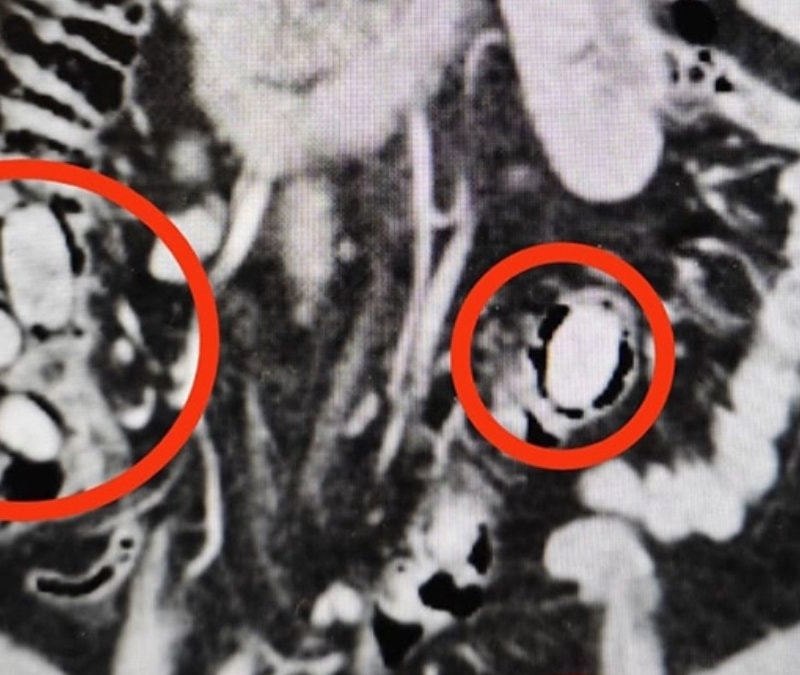

Eskişehir'de midesinde 44 kapsül sentetik uyuşturucu olduğu belirlenen yabancı uyruklu şüpheli tutuklandı.